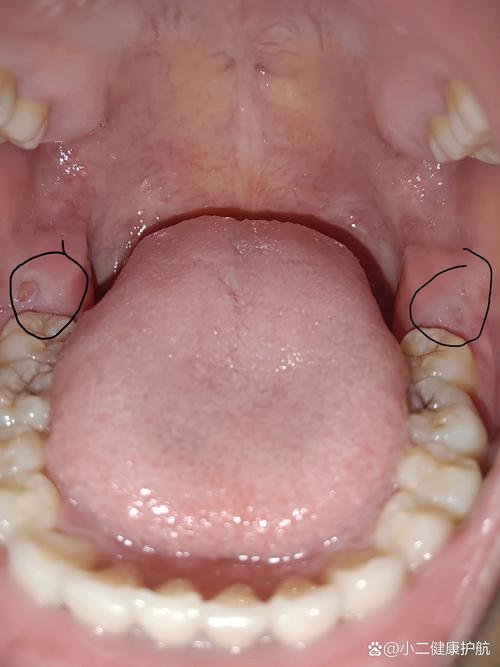

在早期阶段,当智齿开始萌出时,很多人会感到牙龈局部轻微疼痛,这种疼痛通常呈阵发性,可能在咀嚼或张嘴时加剧,牙龈可能会出现红肿现象,用手触摸时能感觉到局部温度升高,这是因为智齿萌出过程中,牙冠顶破牙龈组织,导致牙龈受到刺激和轻微损伤,引发炎症反应,此时口腔内可能会感到不适,尤其是后牙区域,有时还会伴有同侧耳朵周围或下颌角的放射性疼痛,这种疼痛容易被误认为是耳朵或面部其他器官的问题。

随着智齿继续萌出,如果空间不足,智齿可能会倾斜生长,部分牙龈覆盖在牙冠表面,形成一个盲袋,这个盲袋容易食物残渣和细菌积聚,日常刷牙很难彻底清洁,久而久之,细菌大量繁殖,引发冠周炎,这是长智齿最常见的问题之一,冠周炎的症状会明显加重,牙龈出现剧烈疼痛,疼痛可放射至头部、颈部和肩部,导致患者张口受限,甚至无法正常进食,说话和吞咽也会受到影响,此时牙龈红肿更加明显,表面可能出现脓液,按压时有脓液溢出,同时伴有口腔异味,即使认真刷牙也无法消除,严重时还可能出现发烧、头痛、全身乏力等全身症状,颌下淋巴结也可能肿大并伴有压痛。